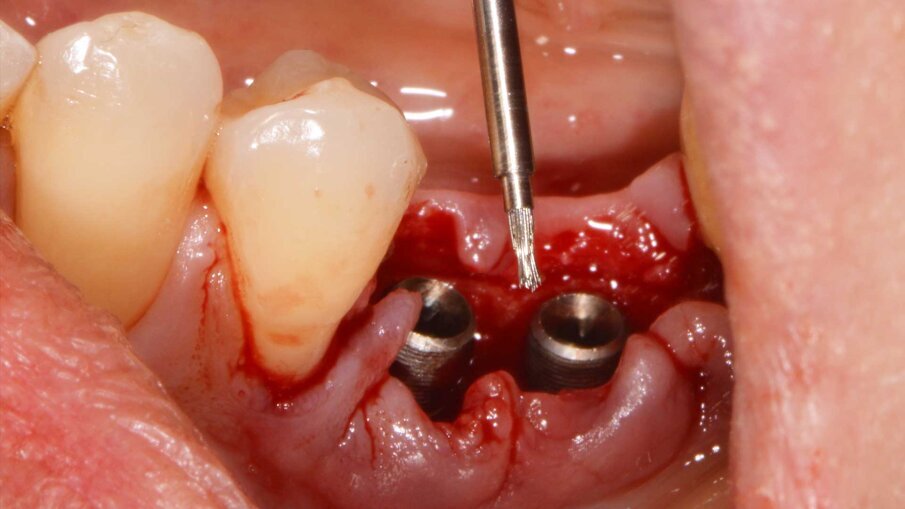

Un paziente di 47 anni, non fumatore e in buono stato di salute, all’esame clinico presenta una perimplantite diagnosticata dopo 7 anni di carico a livello degli impianti 3.5 e 3.6, con un sondaggio di 8 mm sull’aspetto mesiale dell’impianto 3.5 e di 4,5 mm sull’aspetto distale del 3.6. La radiografia conferma la perdita ossea attorno all’impianto distale e ancora più evidente a livello dell’impianto mesiale (Fig. 1). Si decide di trattare il caso chirurgicamente decontaminando la zona affetta, utilizzando il gel REGENFAST per potenziare il trofismo topico e inserendo la matrice Geistlich Fibro-Gide a sostegno dei tessuti molli coronali. Si procede con il trattamento chirurgico, esponendo il difetto per rimuovere il tessuto di granulazione (Fig. 2). La superficie implantare esposta è ulteriormente ripulita con ultrasuoni, spazzolino in titanio, passando all’interno delle spire e risciacquando con soluzione fisiologica e garze sterili (Fig. 3). Successivamente, il gel REGENFAST è dosato e posizionato direttamente all’interno del difetto perimplantare mediante spatolina o puntale (Fig. 4). La matrice Geistlich Fibro-Gide è ritagliata in modalità “Collagen-Ring” affinché possa essere posizionata attorno al collare implantare, sostenendo i tessuti molli che non collasseranno all’interno del difetto (Fig. 5). La matrice, grazie all’elevata porosità è completamente permeata di sangue permettendo la stabilizzazione del coagulo. La matrice viene ulteriormente imbevuta di gel REGENFAST così da potenziare i fisiologici processi rigenerativi (Fig. 6).

Fig. 3 - Decontaminazione della superficie perimplantare.